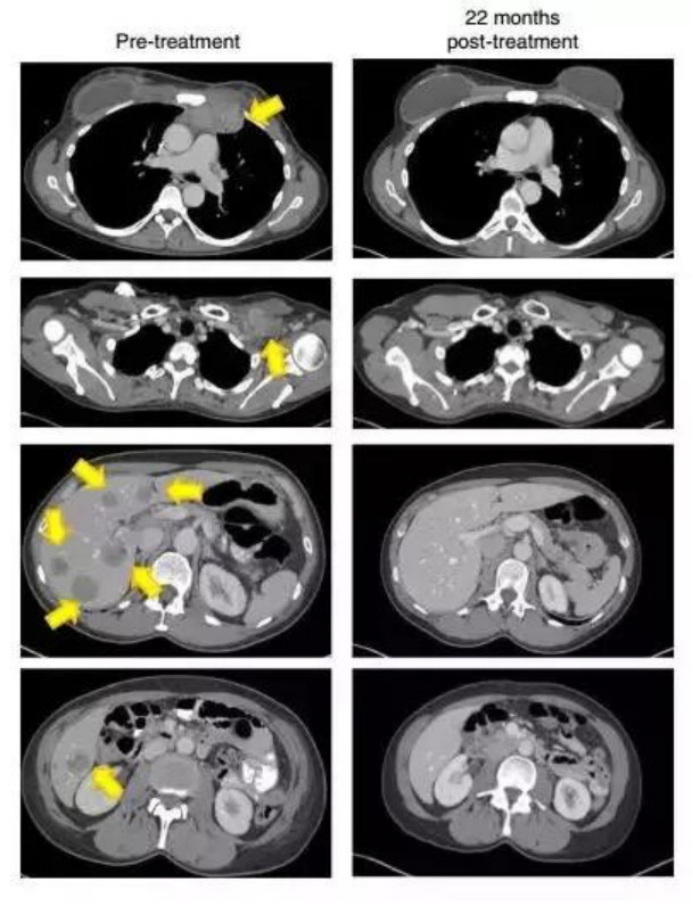

2.晚乳腺癌接受治疗22个月后,这名患者的肿瘤(黄色箭头)消失得无影无踪

(图片来源:《Nature Medicine》)